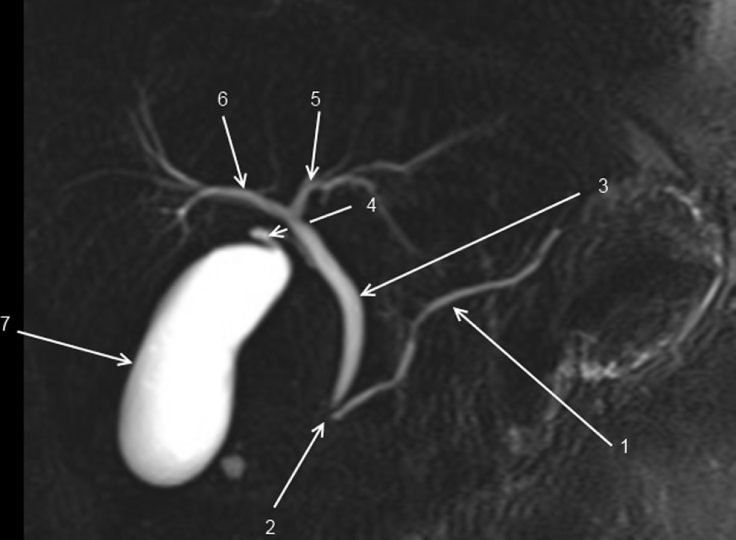

Fig. 2.5 Vue frontale d’une séquence de cholangiopancréatographie IRM où seules les structures contenant du liquide immobile sont visibles.

1. Conduit pancréatique (de Wirsung). 2. Sphincter de l’ampoule hépatopancréatique (d’Oddi). 3. Conduit cholédoque. 4. Conduit cystique. 5. Conduit hépatique gauche. 6. Conduit hépatique droit. 7. Vésicule biliaire.